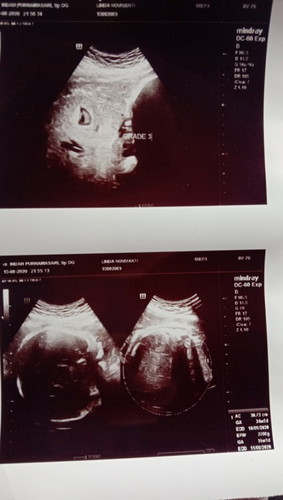

Bismillah sebelumnya mau ngucapin jazakillah khair buat bunda semua yg udah doain sya, kemarin smpat ngepost tentang hpl yg udah mau lewat tpi blm ngerasain apa2 alhamdulillah hari ini tepat hpl udah ada kontraksi dan stelah cek vt udah bukaan 2 bun, semoga bunda semua yg hpl september segera merasakan gelombang cinta jga yah dari sikecil #Alhamdulillaah